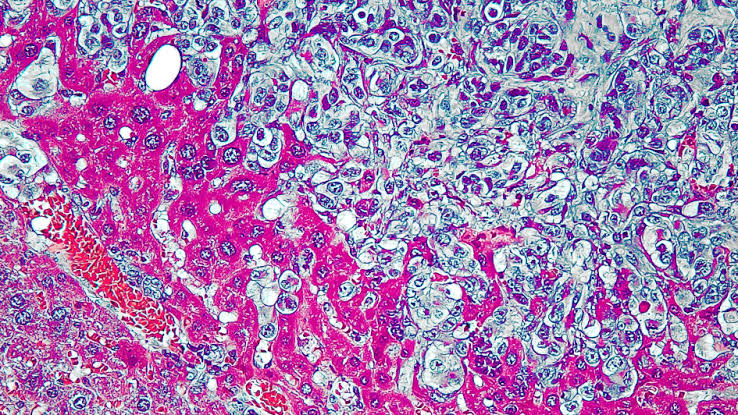

Yumuşak doku sarkomları tüm yetişkin kanserlerinin %1’den azını oluşturur. Nadir görülen ve pek çok alt tipi bulunan heterojen bir hastalık grubudur. Tedavide en iyi sonuçlar tümör etrafında yeterli salim doku bırakılarak tam olarak cerrahi tam rezeksiyon şeklinde çıkarılması ile elde edilir. Erken evrede teşhis edilip cerrahi ile tam olarak çıkarılabilen hastaların yarısında zaman içinde yaygın hastalık ortaya çıkabilir. Bu nedenle bazı hastalarda cerrahiye ek olarak koruyucu radyoterapi ve kemoterapi uygulanabilir. Cerrahiye uygun olmayan lokal ileri veya metastatik hastalıkta sistemik tedavi yapılması gerekir. Sistemik tedavinin amacı hastalığın kesin tedavisinden ziyade tümör kitlesinde küçülme sağlanarak hastanın hayat kalitesinin artırılması ve yaşam süresinin uzatılmasıdır.

Yumuşak doku sarkomları heterojen bir hastalık grubu olmasına rağmen tedavileri birbirine benzerdir. Buna rağmen hastalık gidişatı ve kemoterapiye yanıtları oldukça farklı olabilmektedir. Metastatik hastalık birinci seride doksorubisin tek ajan tedavisi ve uygun endikasyonlarda ifosfamid ile kombinasyonu (IMA rejimi) standart tedavi yaklaşımı olmaya devam etmektedir. Pek çok yumuşak doku sarkomları alt tipi kemoterapiye primer dirençlidir. Hedefe yönelik tedavilerle birlikte kemorefrakter olan sarkom tiplerinde de olumlu sonuçlar alınmaya başlanmıştır. Günümüzde tüm bu tedavi alternatiflerine rağmen ileri evre hastalıkta tedavi için yeni gelişmelere ihtiyaç vardır